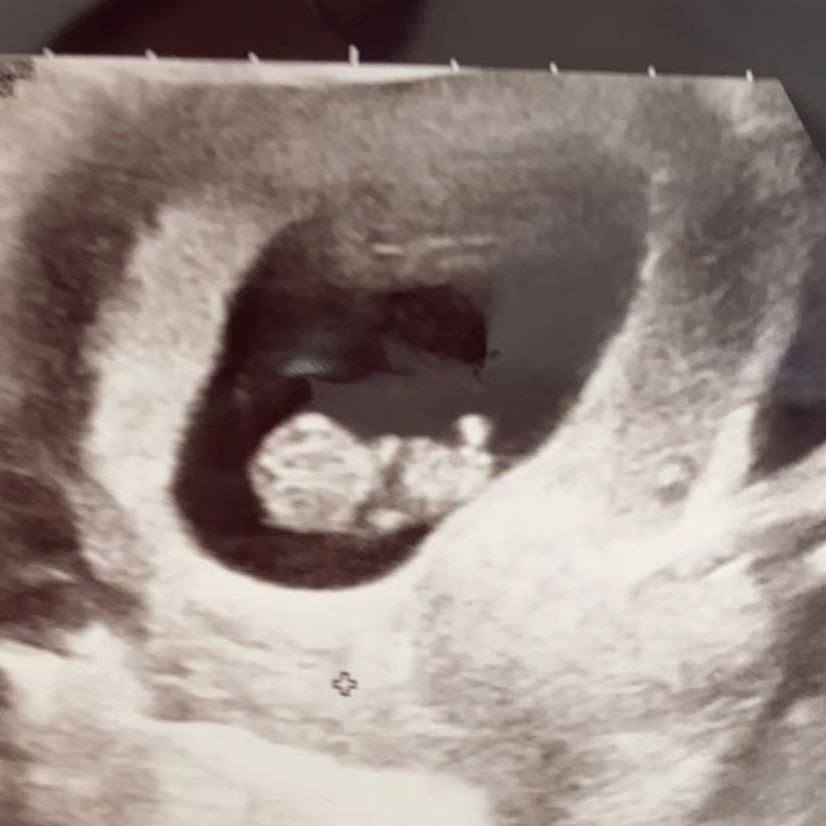

양수는 태아를 지켜주는 생명의 물입니다. 특히 양수의 양은 태아의 안전과 밀접한 관계가 있기 때문에 정기검진 시마다 측정하는 게 바람직하죠.

자궁강을 채우는 액체로, 모체의 혈액 성분인 혈장의 일부가 양수로 만들어진다. 임신 중기에는 태아의 얇은 피부를 통해 체액이 배어 나와 양수를 만들기도 하고, 태아의 몸속으로 양수가 흡수되기도 하며, 피부의 기공을 통해 배출된 수분이 새로운 양수가 되기도 한다. 하지만 임신 16주가 지나면 피부의 기공이 서서히 닫혀 양수가 피부를 통과하지 못하고, 이때부터 태아의 소변이 양수의 주요 공급원이 된다. 임신 초기의 양수는 무색으로 투명한테, 임신 후기가 되면 태아의 피부에서 박리되는 상피세포, 태지, 솜털, 소변 등이 섞여 흰색 또는 노르스름한 색을 띤다.

태아는 엄마 배속에서 팔다리를 움직이고 몸의 방향을 트는 동작을 반복하면서 근육과 골격이 발달한다. 태아가 이처럼 자유롭게 움직일 수 있는 것은 양수에 떠 있기 때문이다. 폐 발육에도 지대한 영향을 미친다. 양수 속에서 생활하면서 폐가 발달한 태아는 태어나자마자 스스로 호흡한다.